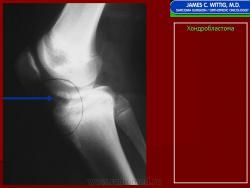

Рентгенологически хондробластома представляет собой сравнительно большой (2-4 см) очаг округлой формы, четко отграниченный от окружающей кости склеротической каймой. На фоне очага в большинстве случаев, но не обязательно определяются плотные включения, напоминающие хлопья ваты.

Рентгенологическая картина. Хондробластома выглядит как небольшой, от 3 до 6 см литический очаг, центрально или эксцентрично расположенный, с четкими контурами, занимающий около половины площади эпифизарной зоны. Хондробластома плоских костей и мелких трубчатых костей больших размеров, может сопровождаться припухлостью мягких тканей, вздутием кости и периостальной реакцией. Распространение процесса на метафизарную зону встречается часто.

Fig. 19. Chondrobastoma: An expansile lesion involving theepiphysis, physis and metaphysis of the humerus is depicted. The lucent lesion shows cortex destruction and spotty matrix calcifications.